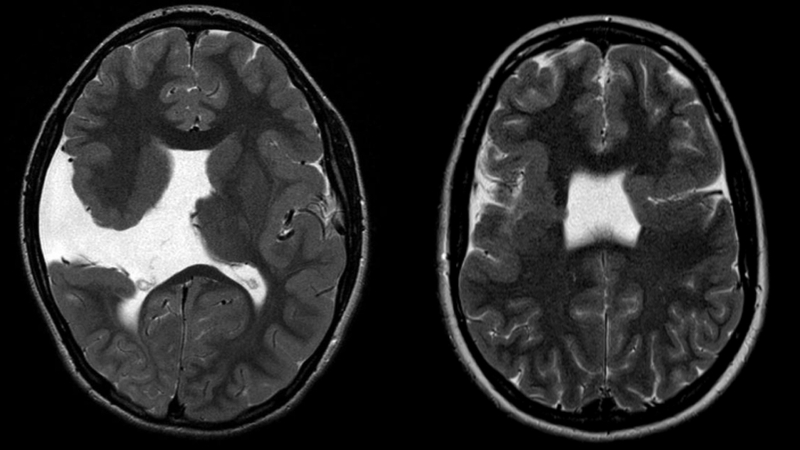

Dị tật chẻ não được chẩn đoán chủ yếu dựa trên các phương tiện chẩn đoán hình ảnh. Về hình thái chung, chúng ta có thể thấy khe hở bề mặt ở một hoặc hai bên vỏ não với các hồi và rãnh não tỏa vào khe hở, là đặc điểm để phân biệt với nhồi máu não giữa trong giai đoạn sơ sinh. Dưới đây là một số phương pháp chẩn đoán phổ biến hiện nay: